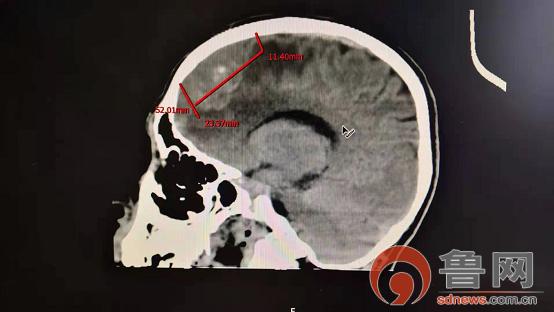

据了解,该病人首次入院是以癫痫为首发症状来诊。入院后对症治疗同时,详细查找癫痫发生的可能原因。颅脑CT中发现患者右侧额叶占位水肿情况,随后行CT、磁共振强化扫描,最终发现导致癫痫根本原因就是右侧额部脑膜瘤。由于瘤体较大压迫周围脑组织,并形成缺血水肿,继而导致癫痫发生。如果肿瘤继续生长,肿瘤越来越大,脑组织受压迫会进一步加重,水肿也越来越重,形成恶性循环,患者有可能出现一系列的症状,如肢体功能障碍、长期卧床、脑疝形成等,生活质量会进一步下降。

如果肿瘤向大脑镰两侧生长,病人可出现双侧肢体力弱,并伴有排尿困难。头颅CT和磁共振,可见镰旁单侧或双侧球形或扁平状占位,平扫时为等密度或略高密度肿块,带有点状或不规则钙化,与大脑镰的基底较宽,一侧侧脑室可受压移位或变形,肿瘤较大时压迫脑静脉,使其回流受阻,脑肿瘤周围可出现水肿。